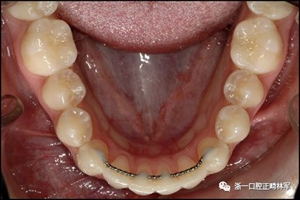

粘合保持器被移除,并放置固定裝置(圖15),僅限于患者要求的下頜弓。在第一階段牙周過程中,將結締組織移植物置于下頜右側中切牙的面側。2個月后進行第二階段牙周過程(圖16)。包括有意識的垂直骨質評分以啟動區域加速現象,以及顯著的面側和舌側植骨以糾正骨開窗。隨著時間的推移,全維度弓絲及其表達的牙齒間扭矩差異顯著改善(圖17)。明智的鄰間減少之后,間隙關閉擴大接觸面,消除不美觀的黑三角。在脫粘之前也校正了牙齒排列和牙弓形態(圖18)。之前和之后的三維圖像(圖19)突出顯示在下頜右側尖牙面側表面上骨的增加以及前牙牙根位置的改善。由于下頜切牙的伸長被認為是不嚴謹的,因此輕度前牙開合沒有被矯正。

正畸文獻閱讀--固定舌側保持器作用下意外的牙齒移動

圖18.脫粘后的最終圖像:A,正面視圖; B,咬合面視圖。 進一步的牙齒移動以糾正輕度前牙開合被認為不符合患者的最佳利益。